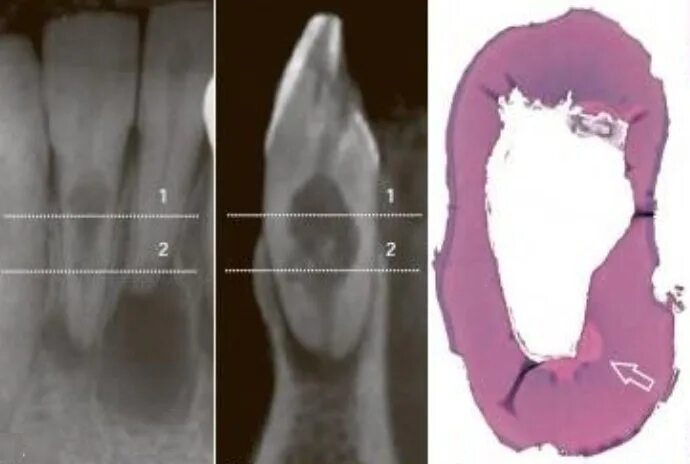

Признаки резорбции